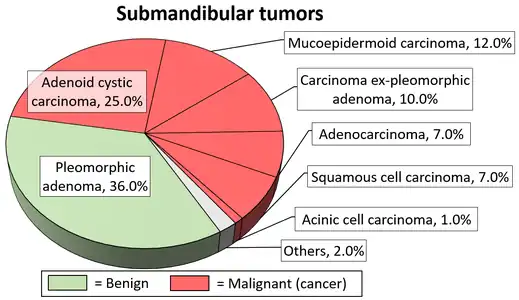

Adenoid cystic carcinoma with comedonecrosis Relative incidence of submandibular tumors, with adenoid cystic carcinoma being the second most common.[17]

Relative incidence of submandibular tumors, with adenoid cystic carcinoma being the second most common.[17] Relative incidence of parotid tumors, with adenoid cystic carcinoma being relatively rare.[17]